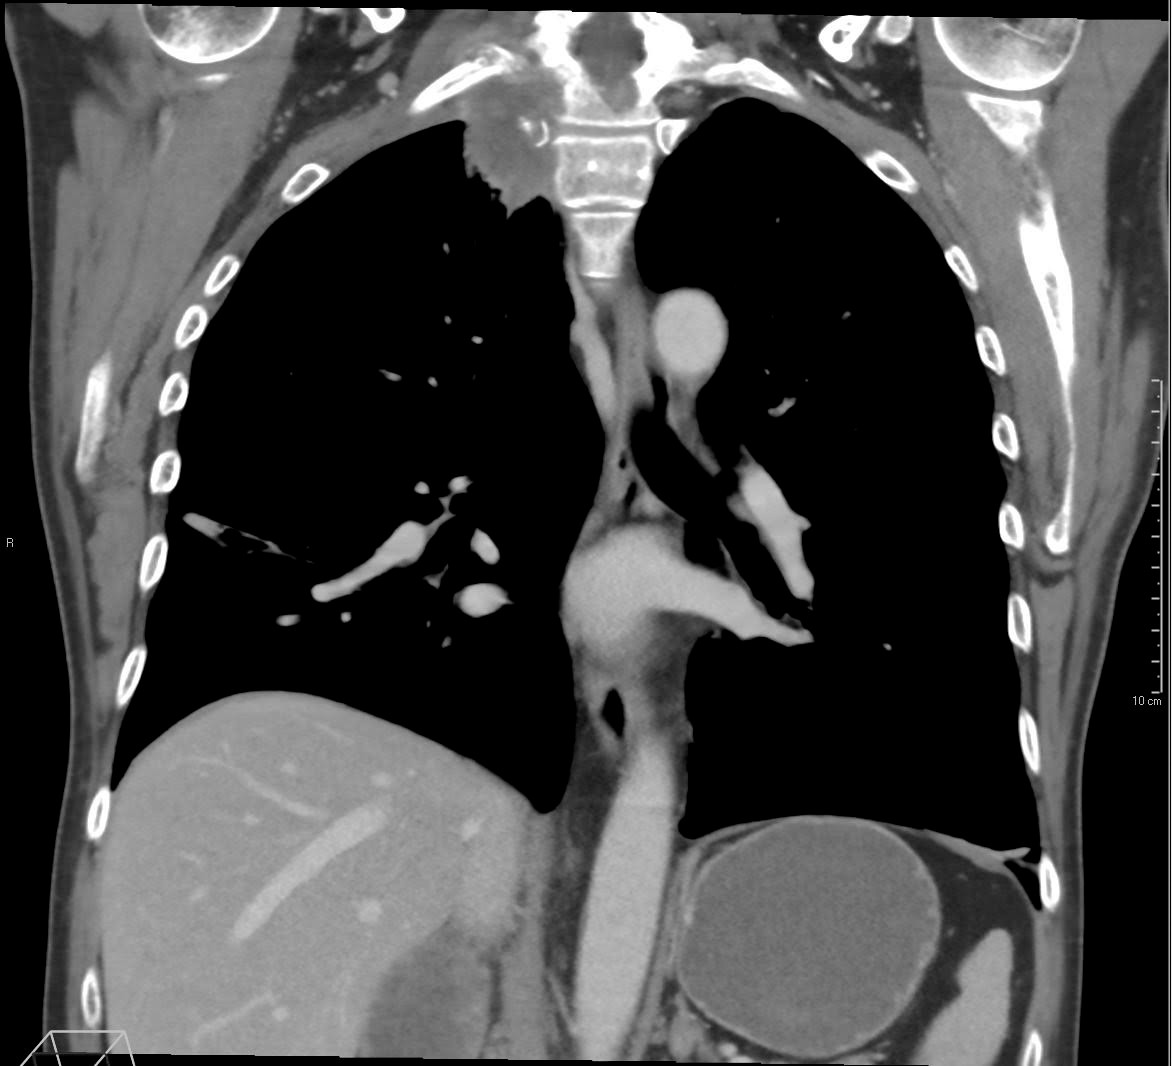

MR av hals og øvre del av thorax ble gjennomført og viste en stor tumor på 4,8 × 2,8 cm i høyre lungeapex. Prednisolon ble seponert, og pasienten ble henvist til CT og MR som bekreftet en tumor apikalt i høyre overlapp (figur 1) med gjennomvekst til costae I og II, corpus vertebrae Th1 og nevroforamina med påvirkning av C8- og Th1-røtter og plexus brachialis (figur 2), innvekst i a. subclavia og metastasesuspekte lesjoner i virvlene C7, Th5, L1, L3 og L4. CT abdomen viste ingen sikre metastaser. Pasienten ble overflyttet til lungemedisinsk avdeling for videre utredning på grunn av mistanke om primær lungekreft.

Lungekreft er et paraplybegrep for flere typer maligne svulster med opprinnelse fra lunger. Disse har ulike mønstre for veksthastighet og spredning og responderer også ulikt på ulike behandlingsregimer (3). Vevsprøver er derfor avgjørende for både diagnostikk og behandling. Flere metoder brukes til å få biopsimateriale, og valget er avhengig av svulstens lokalisasjon til bronkialtreet, forholdet til torakalvegg og andre strukturer rundt tumorvevet.

Pancoast-tumor skyldes som regel malign sykdom. De fleste tilfellene dreier seg om en primær lungetumor, og den vanligste typen er ikke-småcellet lungecancer (9). Andre kreftformer er også beskrevet, som non-Hodgkins lymfom, mesoteliom, myelom samt metastaser fra andre solide tumorer (4). Den perifere lokalisasjonen i lungene gjør at typiske symptomer som hoste, hemoptyse og dyspné sjelden er fremtredende i startfasen av sykdommen. Det er derimot ikke uvanlig at tumoren invaderer nærliggende strukturer som supraklavikulære lymfeknuter, nedre del av plexus brachialis, a. og v. subclavia, pleura parietalis, de øvre ribbena eller ryggvirvlene. Skuldersmerter er ofte det første symptomet. Ved affeksjon av nedre del av plexus brachialis og dens nerverøtter C8 og Th1 kan det oppstå symptomer tilsvarende thoraxapertursyndrom (thoracic outlet syndrome), med utstrålende smerter medialt i overarm, albue og ulnare del av underarm. Etter hvert kan det tilkomme pareser for håndtrykk og fingersprik, redusert sensibilitet og atrofi i ulnare del av underarm og hypotenarmuskulatur. Ofte affiserer den truncus sympaticus og gir Horners syndrom. Tumoren kan også komprimere nn. laryngeus, phrenicus og/eller vagus. Fjernmetastasering er ikke uvanlig. Kliniske funn varierer og er avhengig av den nøyaktige posisjonen til tumoren og hva som påvirkes av de omliggende strukturene.